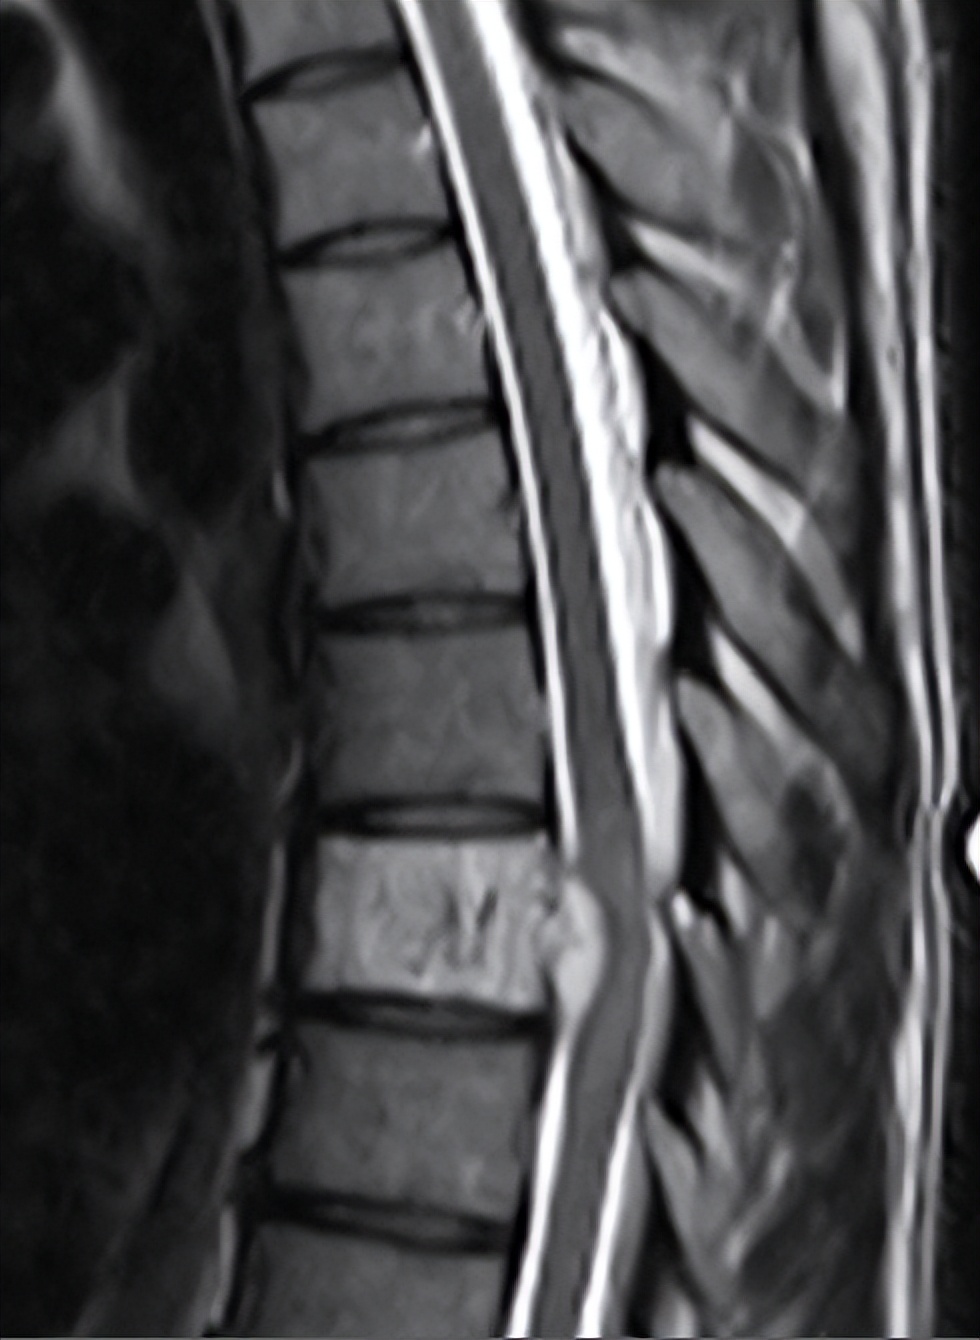

这是血管瘤MR表现,可以看到椎体内血管信号,并未压迫脊髓,所以大多数无症状

这是一例少见的侵袭性椎体血管瘤表现,对硬膜囊产生压迫,此时多有神经症状了,这情况就需要积极治疗了。